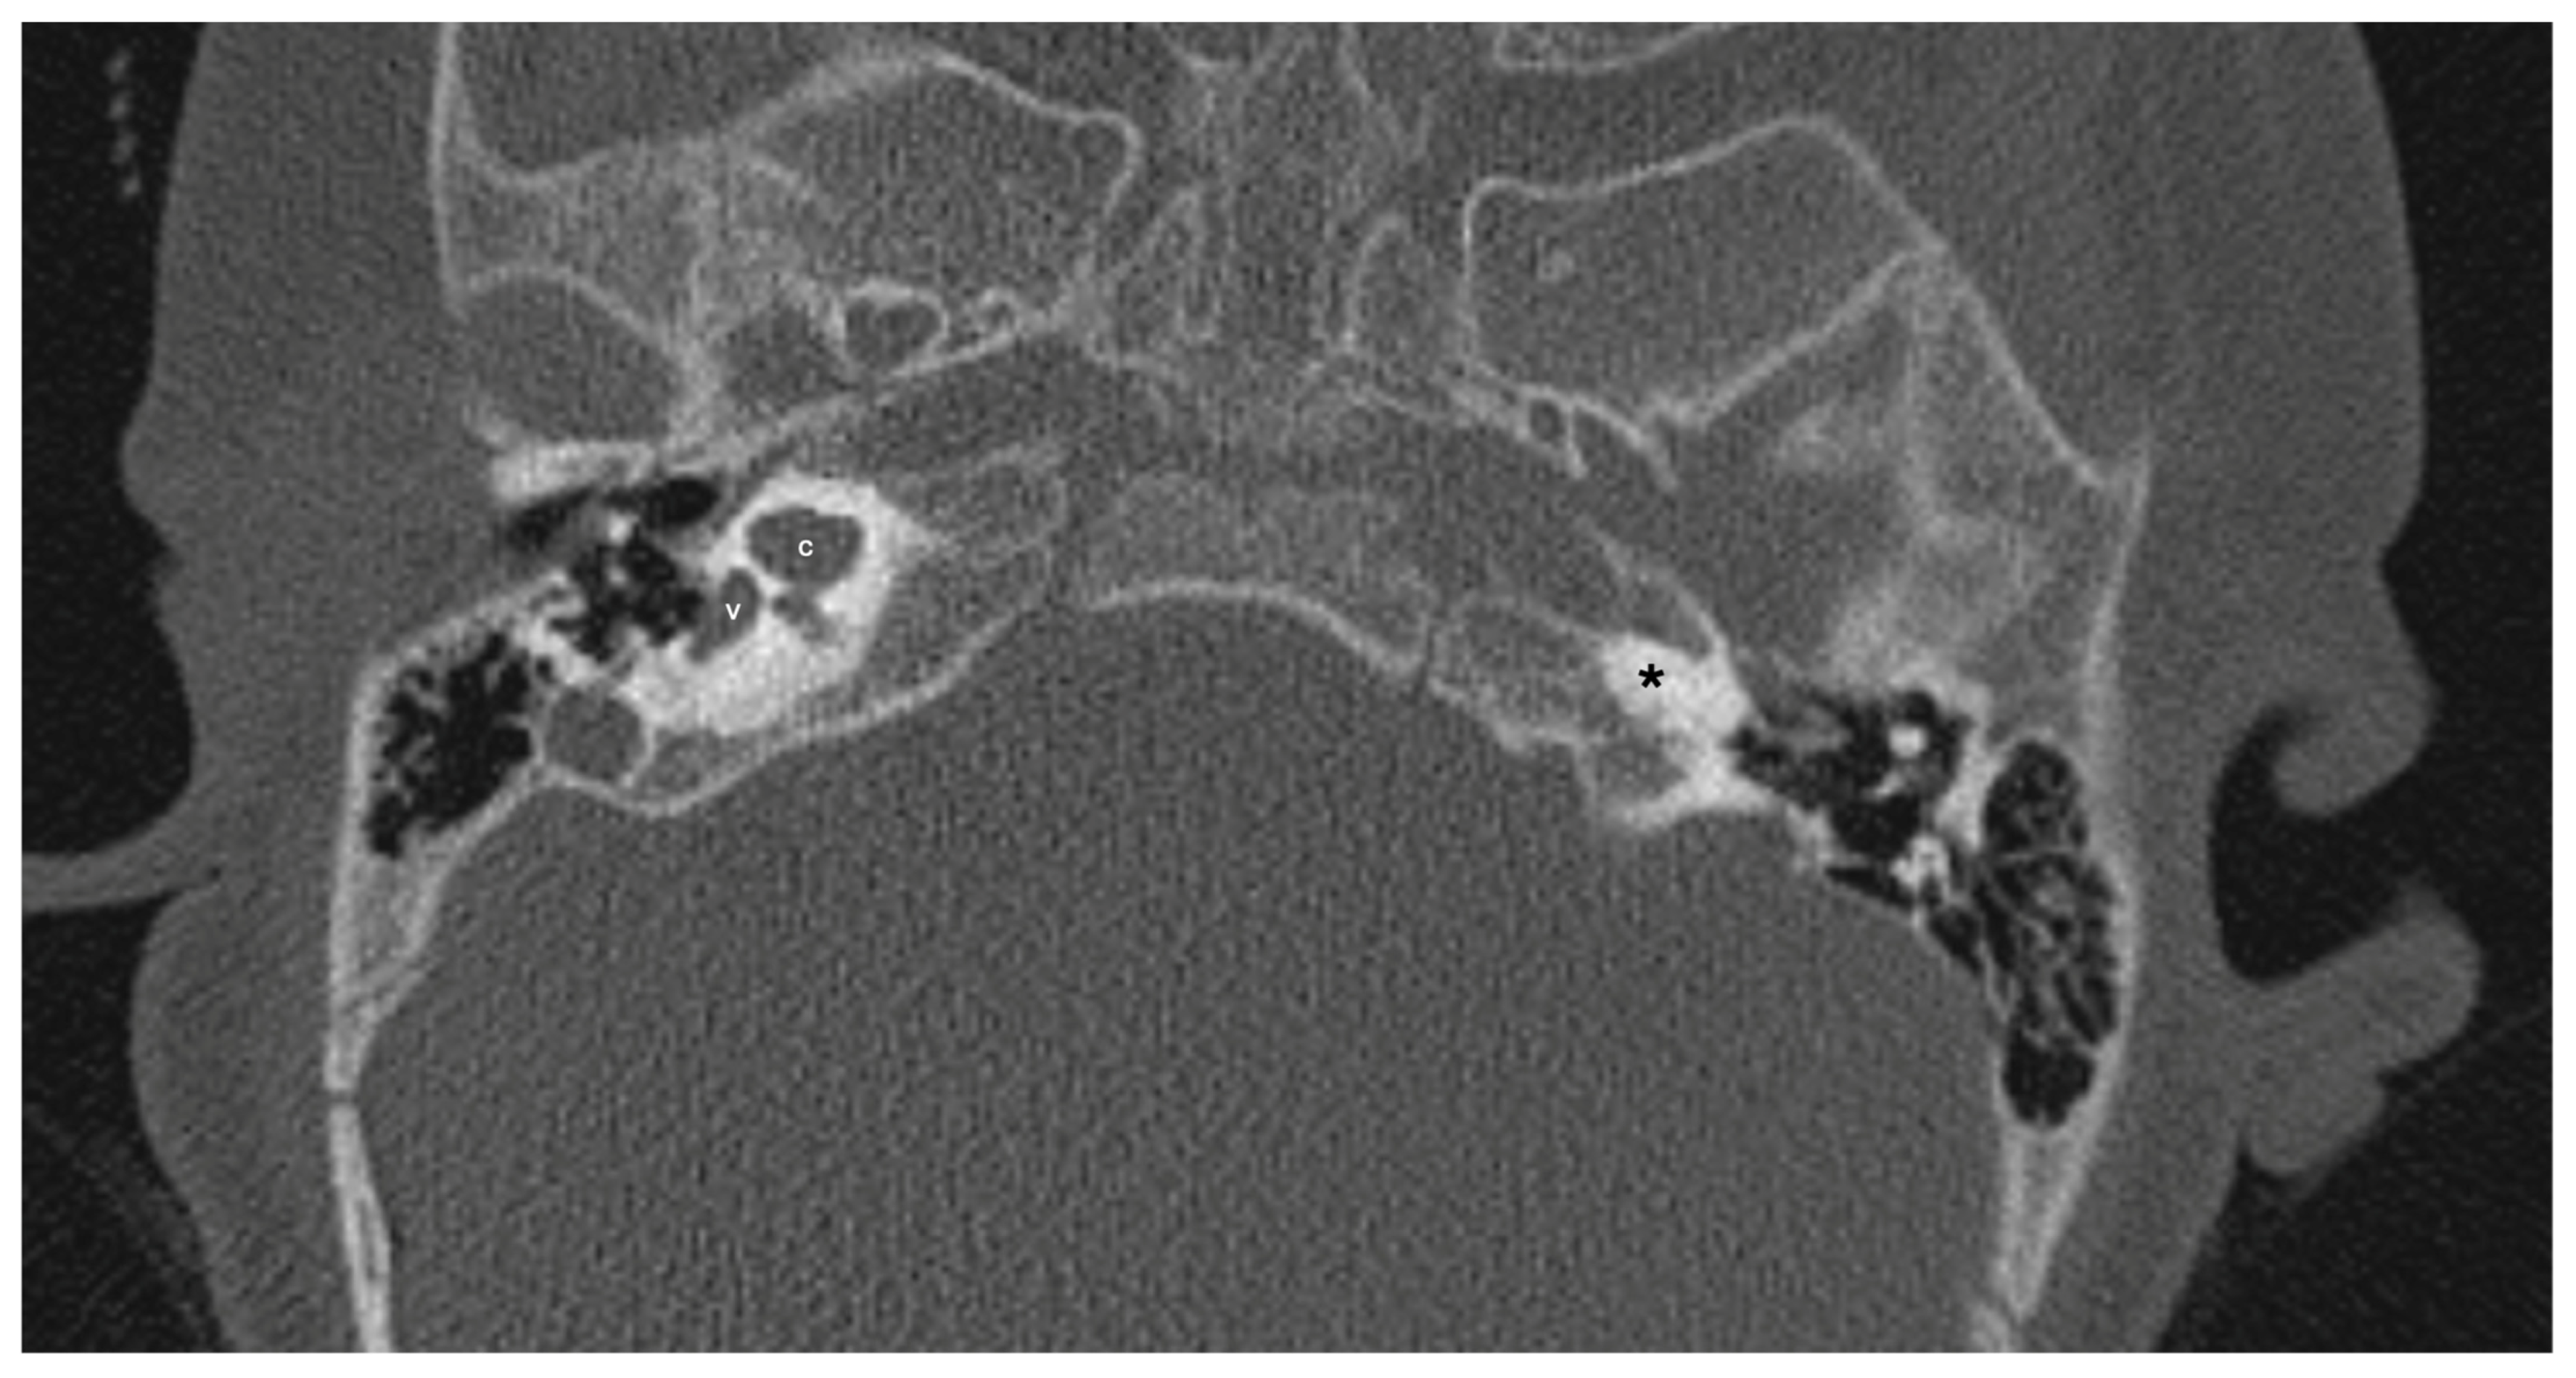

One patient exhibited IP-1 in the right ear and LA in the left ear. The right vestibule was hypoplastic, and the SCCs appeared as a single bud. The diameters of the right IAC and cochlear nerve were within normal limits. However, the stapes, oval and round windows, cochlea, vestibule, SCCs, IAC, and vestibulocochlear nerve could not be detected in the left ear. Cochlear implantation was performed in the right ear of this patient (Figure 3). Bilateral IP-3 anomalies were detected in two siblings. In these cases, the oval and round windows were also malformed. While both cochlear nerves of one sibling exhibited hypoplasia, the cochlear nerves of the other sibling were within normal limits as they were thicker than the facial nerves (Figure 4).

Figure 3.

Patient with right-sided IP-1 (incomplete partition type-1) and left-sided LA (labyrinthine aplasia). On the right side, the cochlea (c) and the vestibule (v) are clearly differentiated. The cochlea has a near-normal size but lacks the entire modiolus and interscalar septa. None of the labyrinthine structures except the dense otic bone (*) can be seen on the left side.